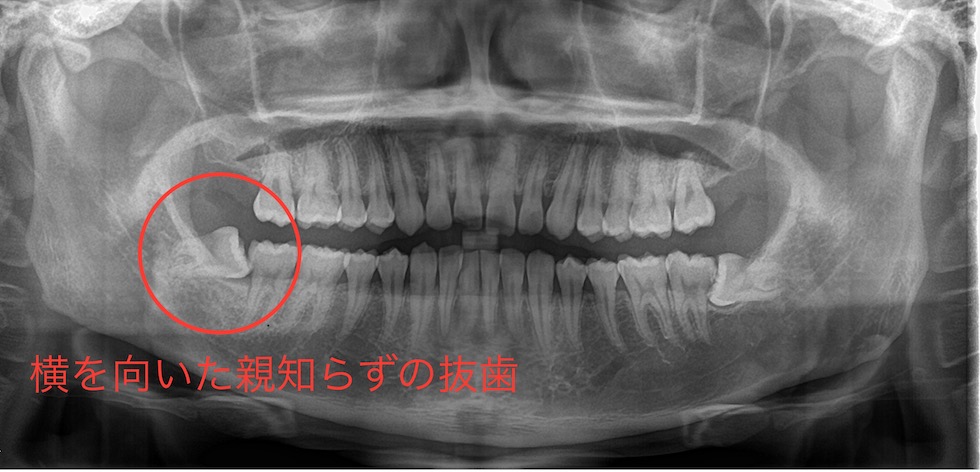

レントゲンで確認したところ、右下の親知らずは斜めに生えていました。手前には健康な歯があり傷をつけられないため、抜歯する親知らずを分割して抜歯をすることになりました。部分麻酔を行ったのち、初めに歯冠(歯の頭の部分)を2つに割って取り、その後、歯根(歯の根の部分)を引き上げることで抜歯を行いました。傷口がやや広いため、1カ所だけ縫合しました。抜歯後の注意事項をご説明し、抗生物質と鎮痛剤を処方しました。